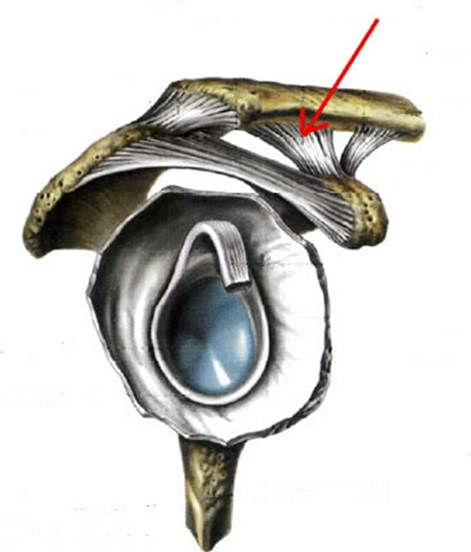

S: Стрелка указывает на art. humeri (латинский язык).

S: Стрелка указывает на lig. coracoclaviculare

Стрелка указывает на lig. trapezoideum

Стрелка указывает на lig. Acromiclavicularis

S: Стрелка указывает на tendo m bicipitis brachii

S: Стрелка указывает на lig. coracoacromiale

S: Цифрой 6 обозначена суставная капсула плечевого сустава (русский язык).